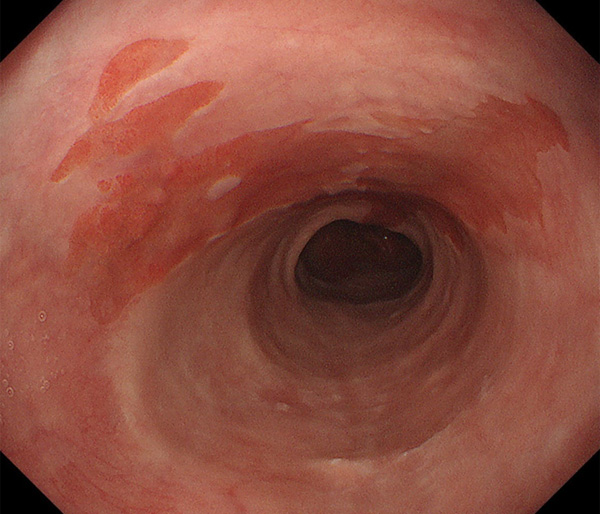

内視鏡所見と病理組織像の1対1対応が可能な症例を公募いたします。主にLSBEに発生した早期癌(HGDを含む)を対象としますが、興味深い症例であればSSBE癌でも結構です。採否は世話人へご一任ください。

症例呈示希望者は応募用紙に記入の上、代表的な内視鏡(2枚)、切除標本(新鮮、固定)、切り出し図、マッピング、代表的組織像とともに、Barrett 食道研究会事務局 barrett.shinshu@gmail.comへお申し込み下さい(10MB以下でお願い致します)。

特に、本邦では極めて稀なlong segment Barrett’s esophagus(LSBE)から発生した早期癌は、診断に難渋する場合も多く、欧米ではランダム生検による検出が標準的とされています。背景のBarrett食道もろとも全体を内視鏡切除+ラジオ波焼灼する欧米と異なり、ESDで内視鏡的な局所切除が基本の本邦では、存在診断+範囲診断(特に水平)を的確に行うことが不可欠です。

そのためには、一流の病理医による組織学的診断とエキスパート内視鏡医による拡大内視鏡像との一対一対応を徹底的に行うことで、『本来、見えないであろう拡大所見の先にある組織構築像が診えてくる』所まで内視鏡診断レベルを上げていく必要があります。その実現には、一対一対応を追究した症例(特にLSBE発生例)1例でも多く経験するしかありません。本研究会でBarrett食道腺癌(LSBE発生早期病変)を共に学び、拡大内視鏡像の一歩先を診るスキルを習得しましょう!一人でも多くの皆様のご参加をお待ちしています。

海外で講演やライブを行う度に、日本と欧米ではBarrett食道癌診断法に大きな乖離がある事を実感します。なぜ、彼らは内視鏡で診断せず、ランダム生検に頼るのか?

私は、Barrett食道癌はHGDも含め、内視鏡による存在診断、範囲診断が可能と信じて来ました。しかし最近、NBI拡大観察を併用しても側方範囲診断が不可能なLSBE症例を経験しました。診断技術を向上させるためには、多くの症例を診るしかありません。そこで、Barrett食道に造詣の深い先生方に世話人をお願いし、Barrett食道研究会を立ち上げることに致しました。全国からLSBE症例を集め、内視鏡的、組織学的診断に迫りたいと思います。皆様のご参加をお待ち致します。